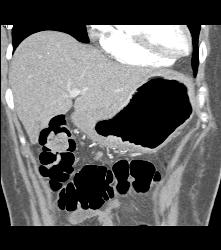

Antral Cancer With Gastric Outlet Obstruction